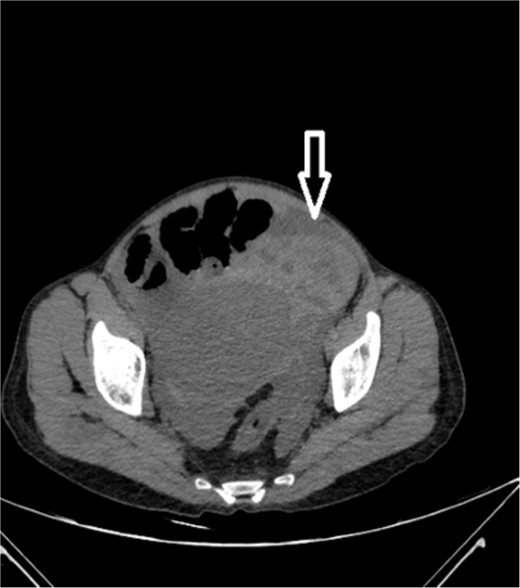

Upon admission to our hospital, the patient’s physical examination revealed hypotension (87/52 mmHg) and tachycardia (150 bpm), along with marked diffuse abdominal tenderness and guarding. Laboratory investigations indicated a hemoglobin level of 7.1 g/dl, a white blood cell count of 14.5 × 103 μl, and a platelet count of 202 × 103 μl. An abdominal CT scan without contrast showed an enlarged ectopic spleen measuring 18 cm in the right abdominal area, a distended stomach, a moderate volume of hemoperitoneum, and significant intra-abdominal fluid accumulation. CT findings are shown in Figs 1–3. Based on these findings, the patient was immediately transferred to the operating room.

Noncontrast axial CT scan of the abdomen showing a perihepatic hematoma.